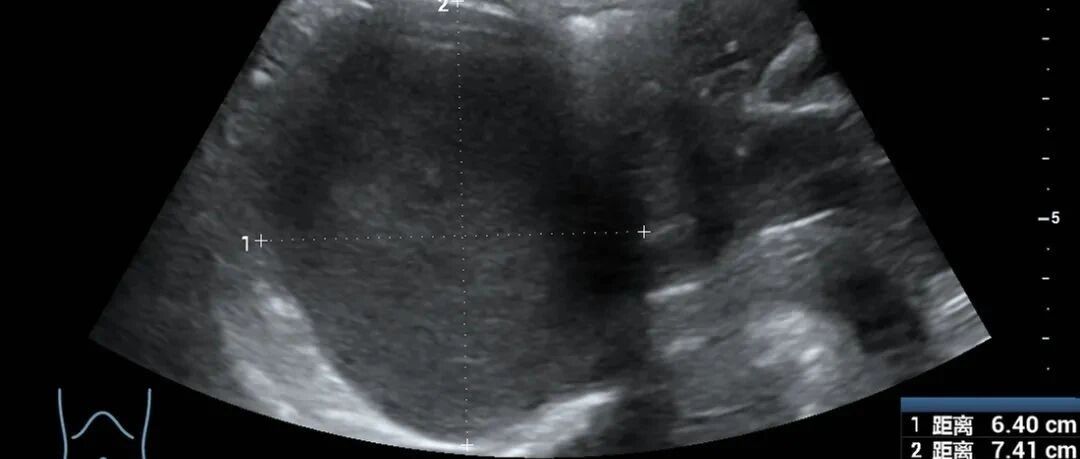

文中一开头那个病例,肝癌破裂出血、失血性休克,这属于非常严重的疾病了,根据他们给我的报告,肝癌已经有多发转移的了,患者营养情况很差,这种病例即便做了介入栓塞止血,效果也不一定好,很可能就定格在ICU了,这个时候可以考虑回家。但也不一定,出血也分严重程度,有些肝癌破裂出血没那么严重,全身情况还行、病变局限,甚至都可以做急诊肝切除治疗。